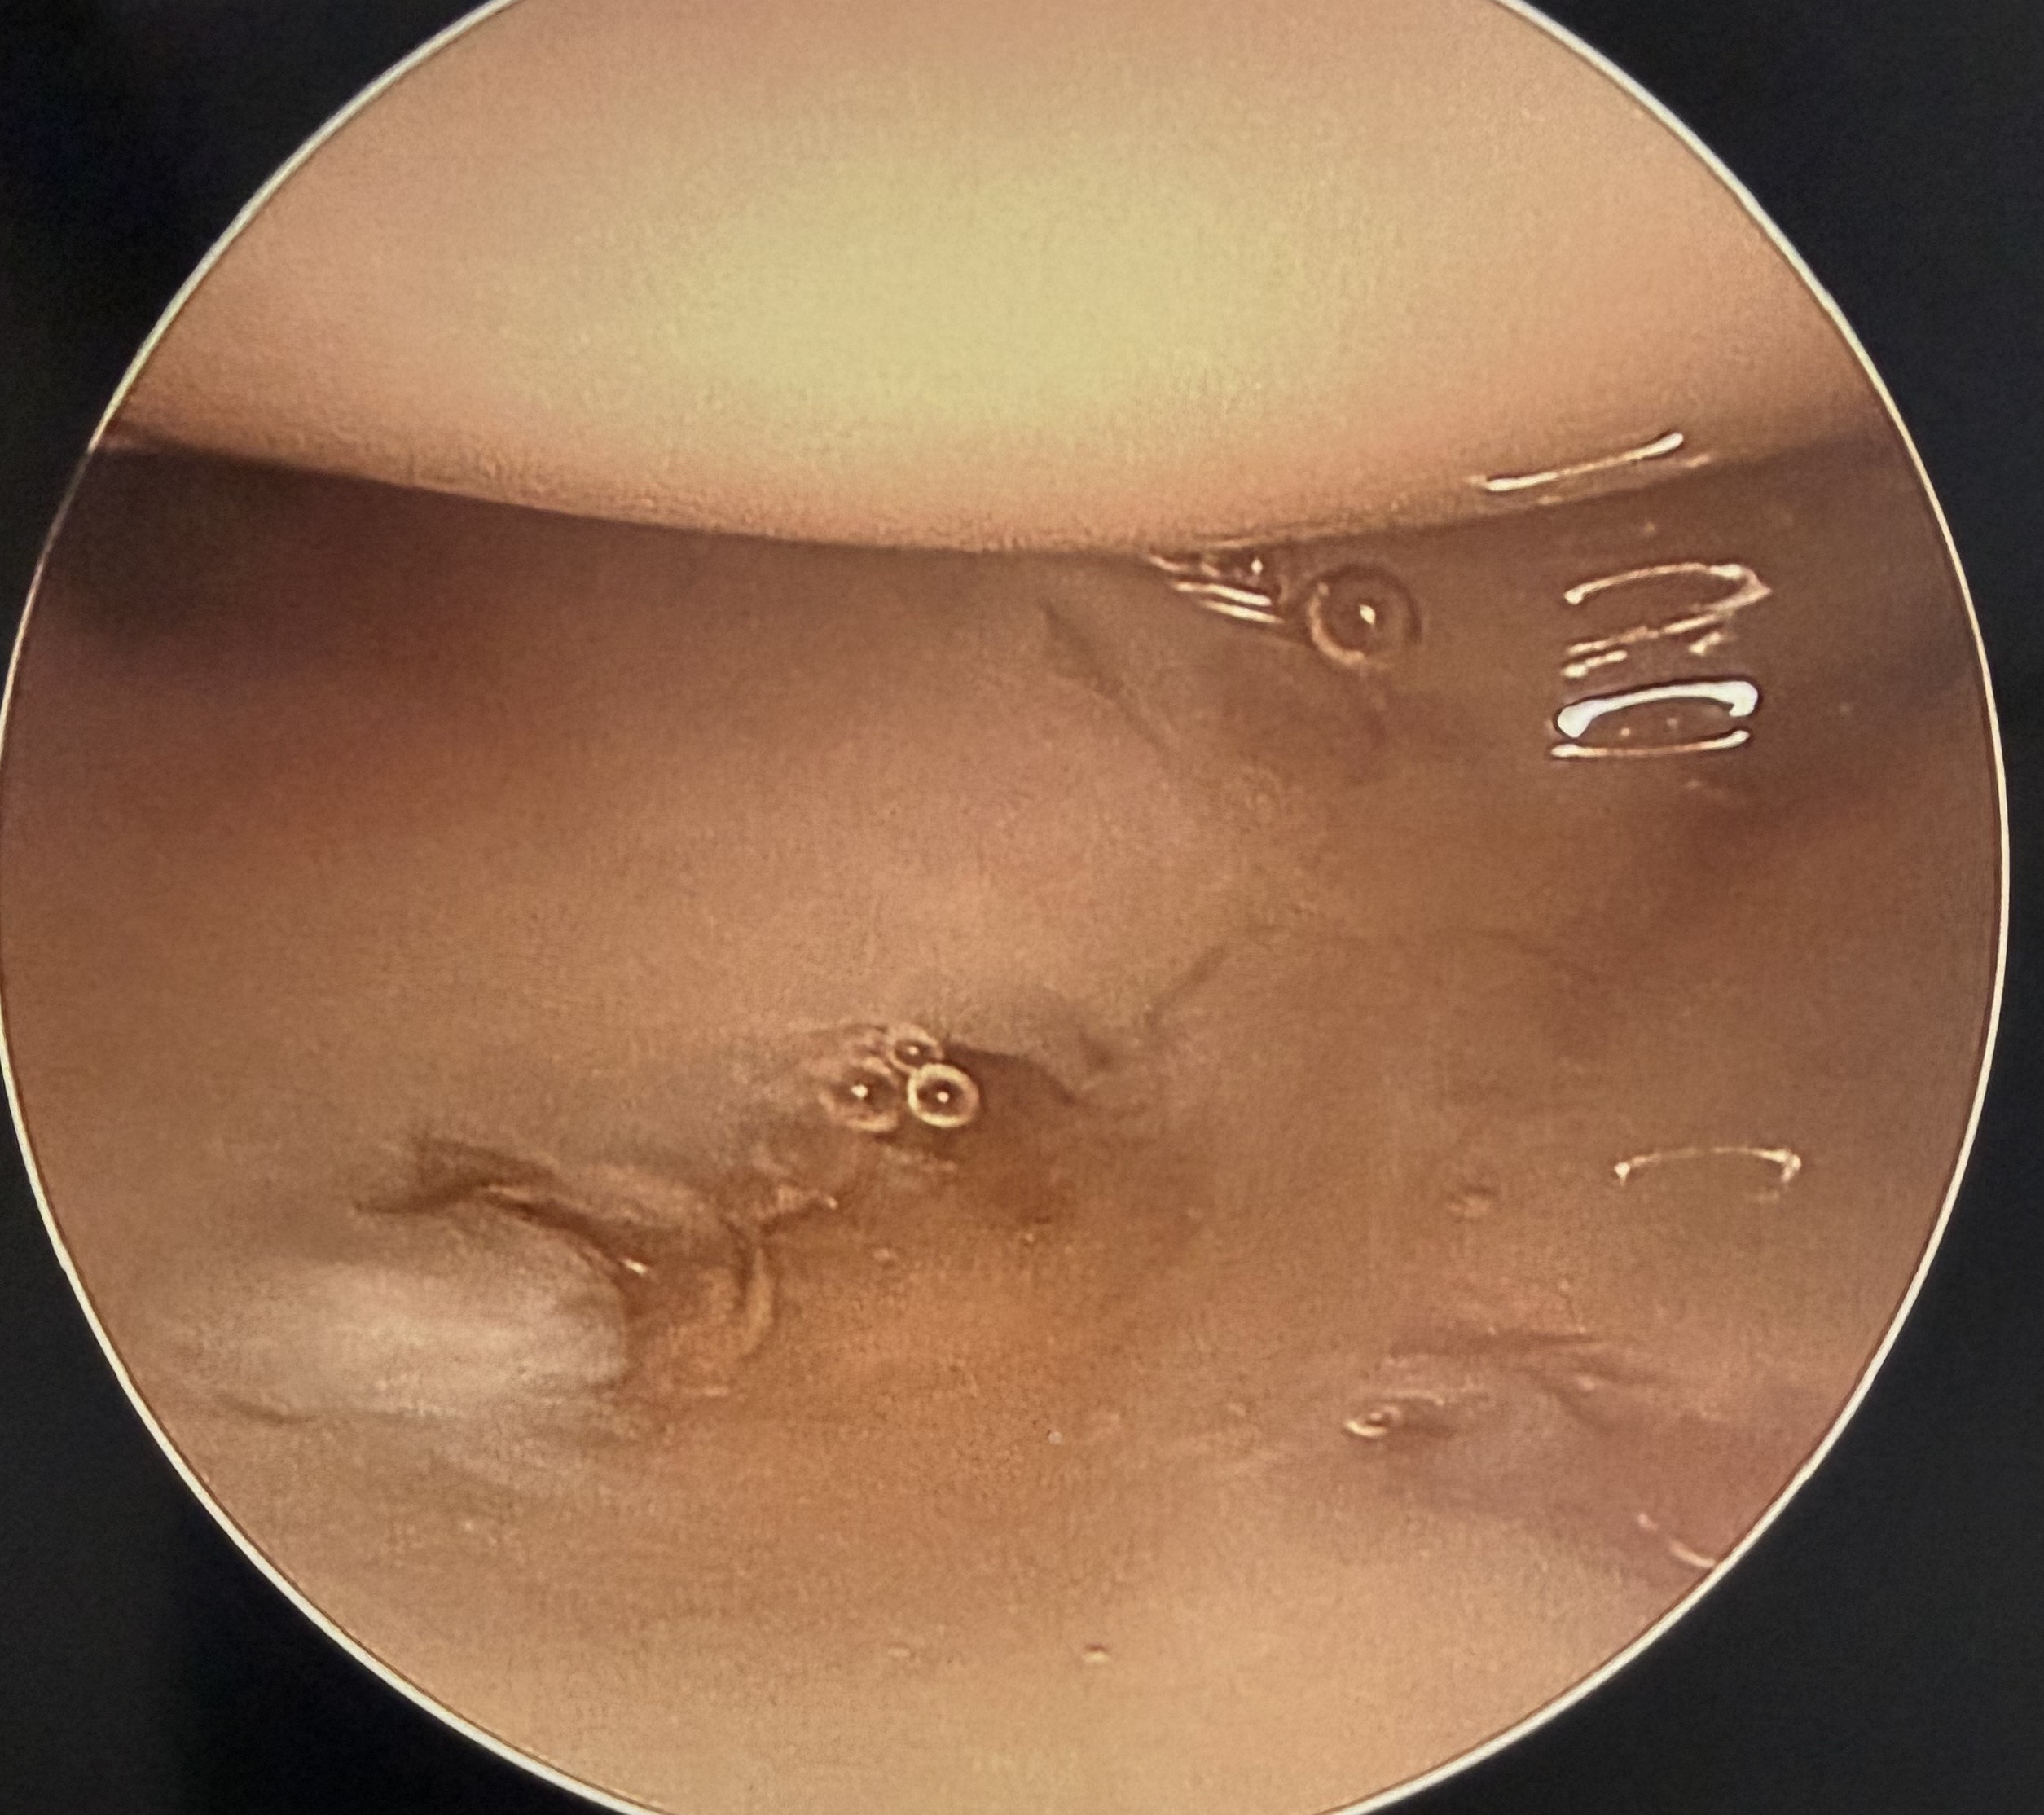

Ulna / foveal sided TFCC tear on arthroscopy

Technique

- viewing via 3-4 portal

- instrumentation via 6R +/- 6U portal (either side of ECU)

- pass outside in and suture over capsule

- suture anchor repair

- drill hole in ulna